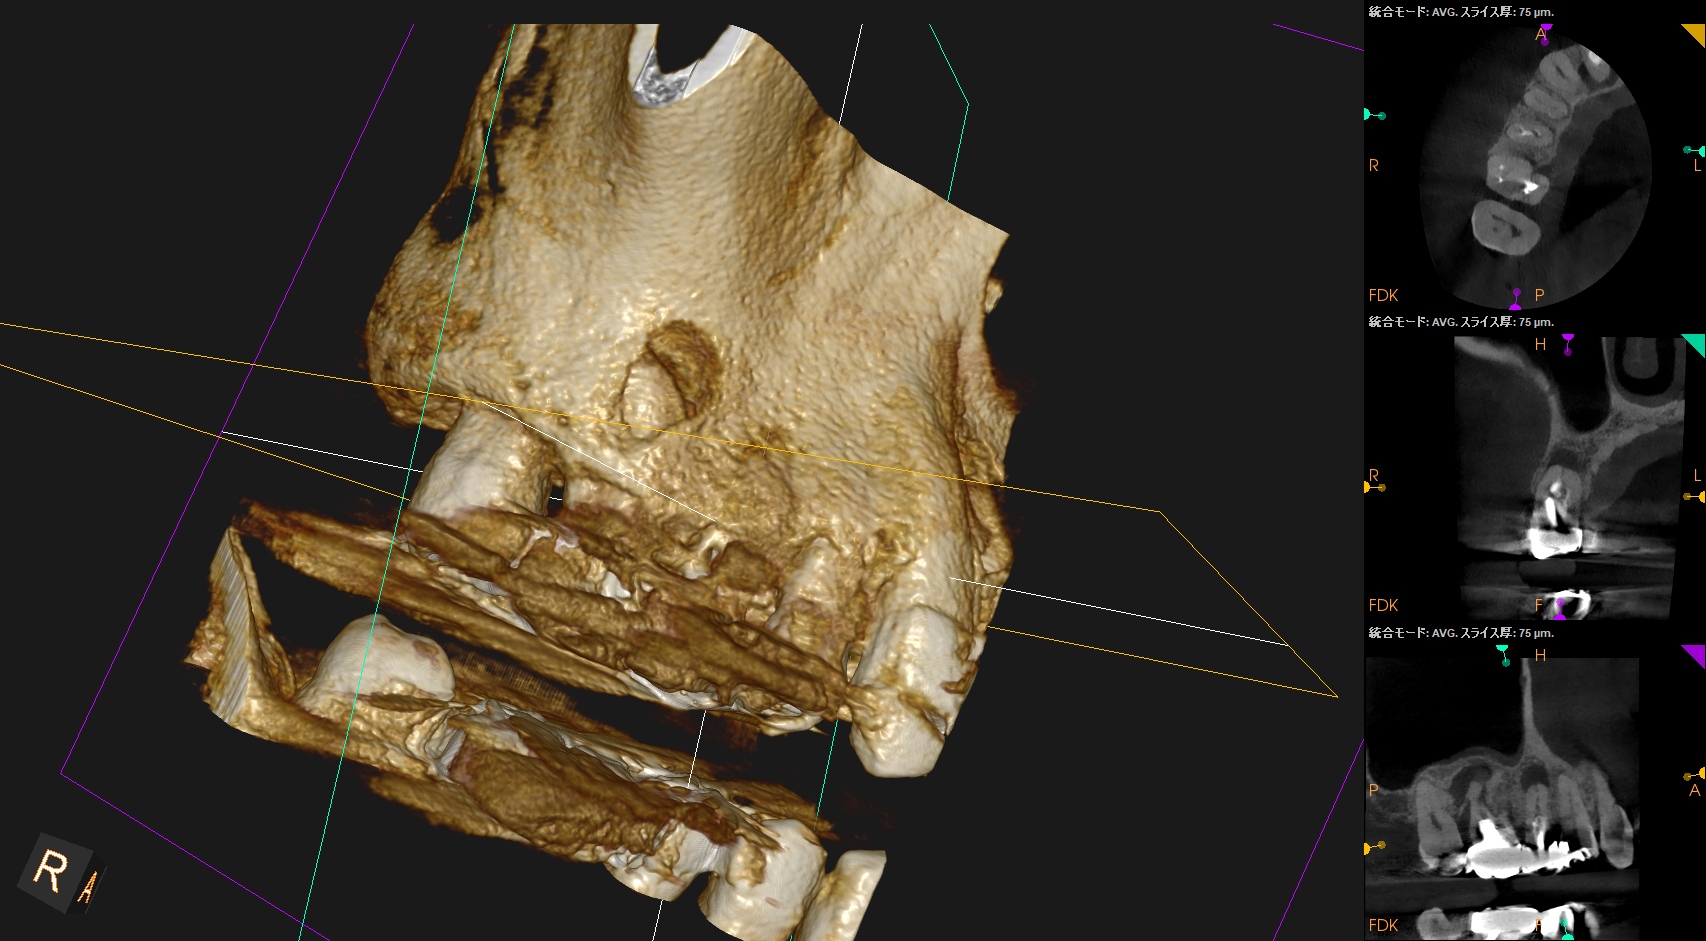

CBCT(2025.9.22)

#4

#3 MB

DB

P

これで抜歯とは…意味がわからない。

このCBCTの絵でこの結果が想像できるだろうか?

このことから何が言えるか?と言えば、

CBCT画像からのみ根尖部の解剖学的形態・状態を推し量るのは無理である

という臨床的事実だ。

再根管治療は実際にFileを根管の中に入れないとそれに意味があるかどうか?はわからないのである。